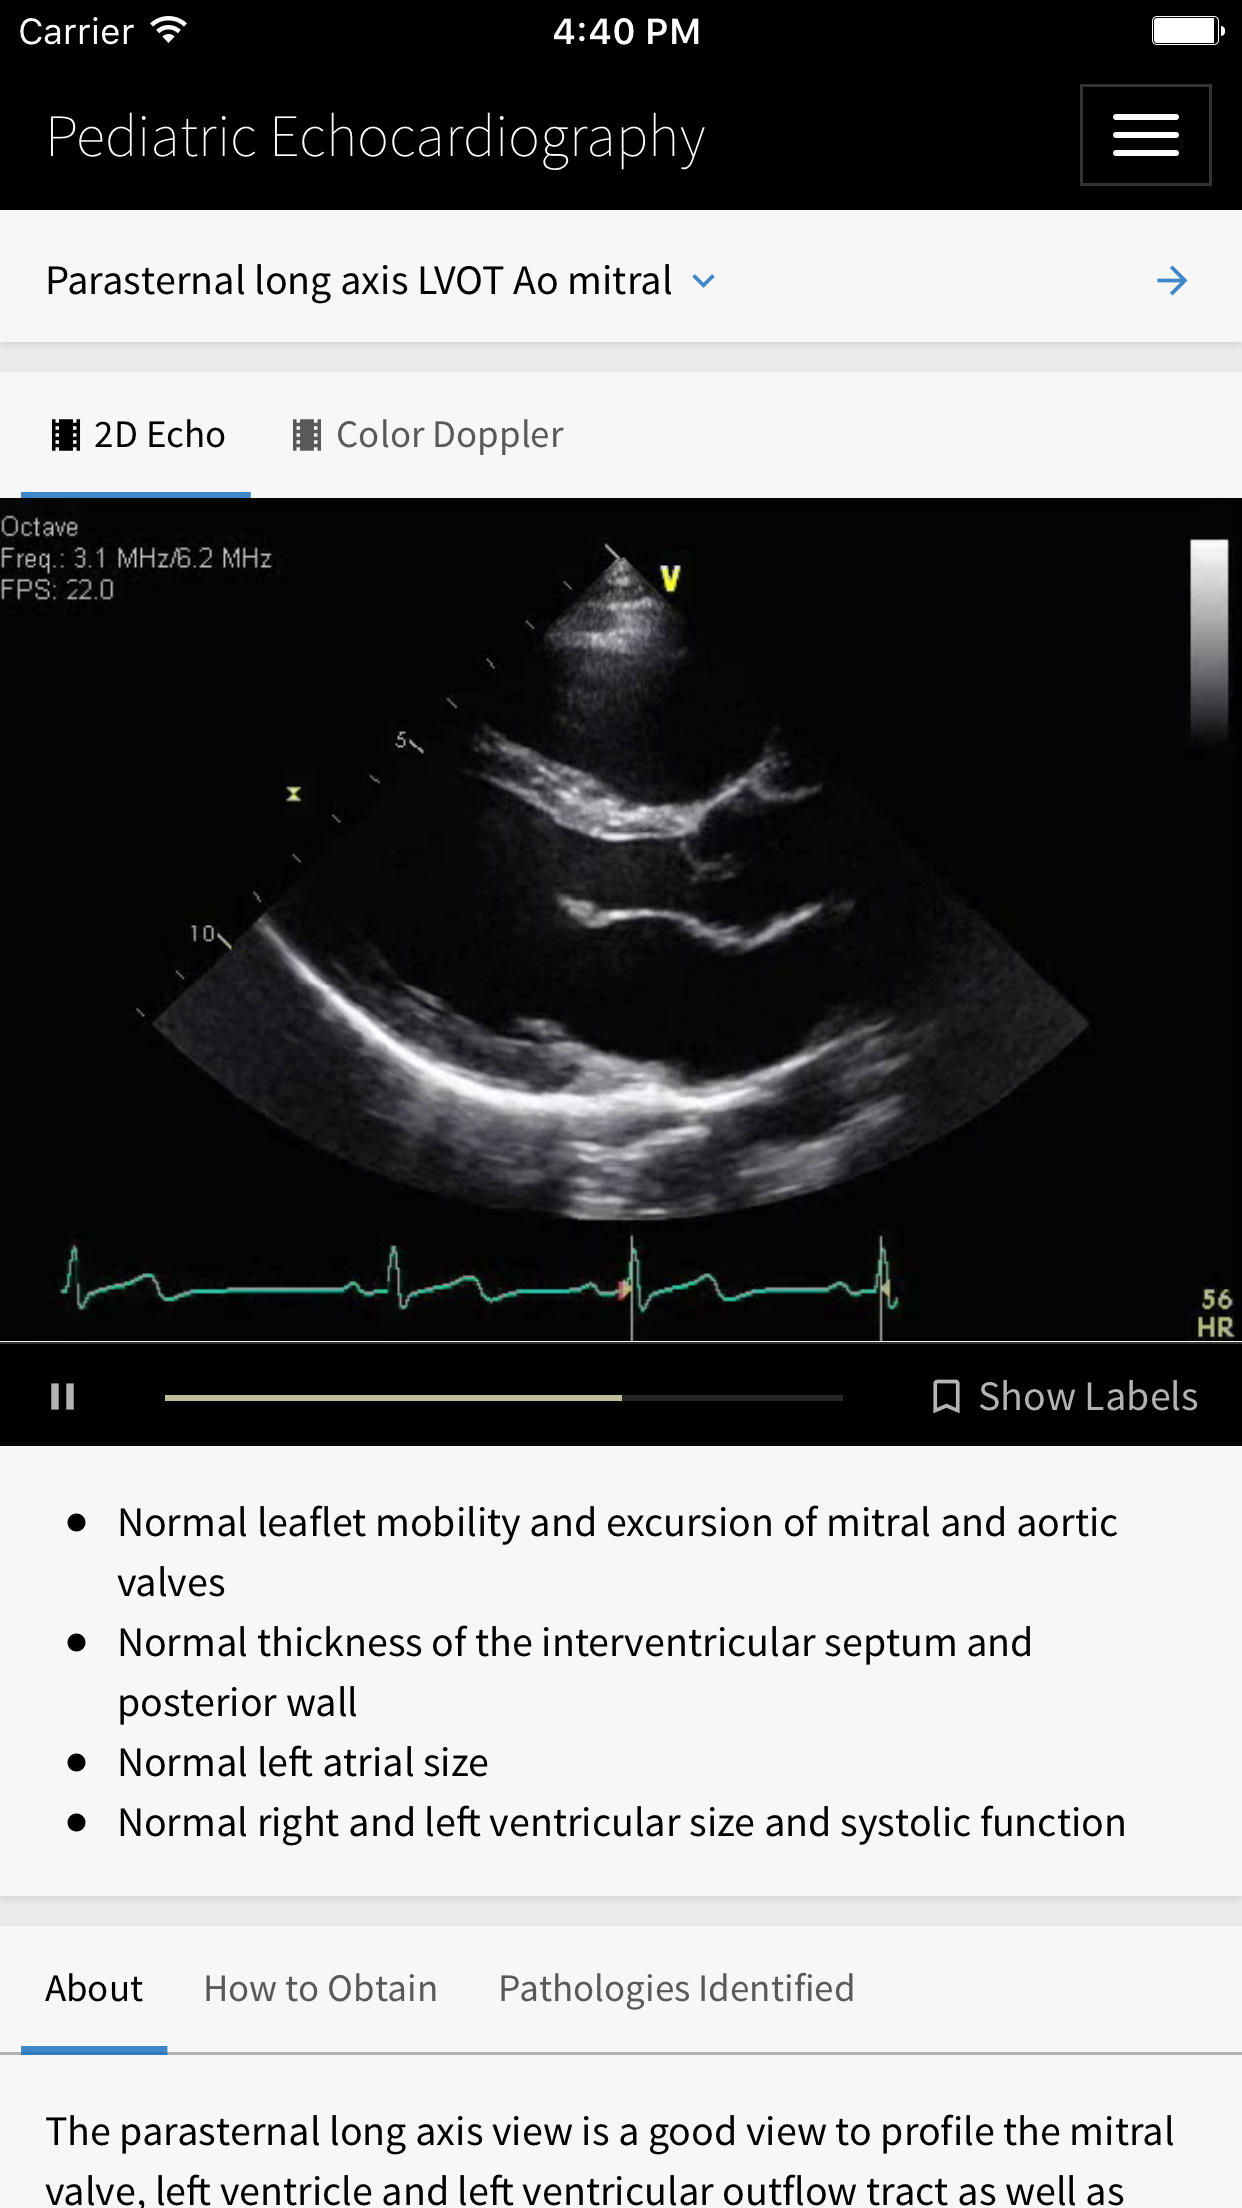

Echocardiography has become an essential technology and is utilized by the majority of pediatric cardiologists. It serves as an indispensible tool in the diagnosis and treatment of congenital heart disease. It involves mastering a complex skill set made up of two key components: procedural echocardiography and interpretive echocardiography. The goal of this app is to provide a background in interpretive echocardiography in the setting of basic and complex congenital heart disease. Congenital heart disease (CHD) is a spectrum of disease from a small hole in the heart to very complex congenital abnormalities. Training physicians and sonographers in echocardiography is a challenge. Cardiologists are expected to not only master a procedural skill, but they are also faced with the challenging task of interpreting those images. Because some types of CHD are quite rare, it is often difficult for trainees in smaller institutions to get exposed to these rare variants. *** Educational Objectives *** - To provide comprehensive training in interpretive echocardiography. - To expose trainees to all variants of congenital heart disease and their subtypes. - To provide a better understanding of normal echocardiographic anatomy. - To allow an interactive approach to reviewing and identifying echocardiographic examples of normal anatomy and congenital heart disease. - To ultimately allow for better identification of cardiac pathology in the clinical setting. *** Target Audience *** This app is meant to serve as an learning resource for medical students, residents, cardiology fellows, cardiologists and sonographers. It provides a comprehensive echo imaging database of fetal and transthoracic echocardiography. In addition, three introductory learning modules (normal anatomy, atrial septal defects and ventricular septal defects) are offered along with with pre and post testing to assess the user’s baseline knowledge and improvement following completion of the learning modules. All answers and scores on the pre and post test are provided to the user upon completion of the post test (the post test becomes available once all views from all three modules have been viewed).